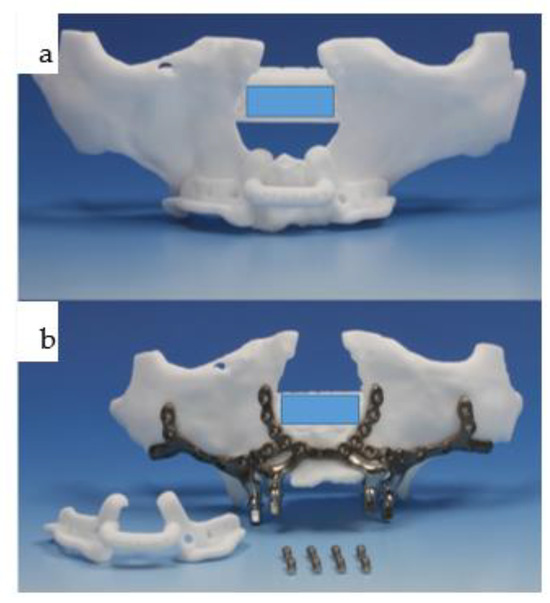

Amazon.com: ビジュアル歯科臨床解剖: 9784781207391: 朱虹: Books。The Use of 3D Technology in the Management of Residual。Concomitant Temporomandibular Joint Replacement and。すべての歯科医師のための臨床解剖学に基づいたComprehensive Dental Surgery折れや破れは無いかと思います。8000円→7500円にお値下げしました。8月14日さらにお値下げしました。。Validation of a patient-specific system for mandible-first。Molecular Biology of the Gene 遺伝子の分子生物学。犬と猫の皮膚病Q&A